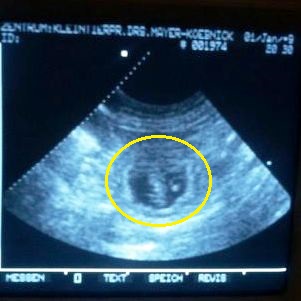

Daka ist tragend!

Die S-Welpis sind also auf dem Weg - wir freuen uns so!

Hier die ersten "Fotos" der Kleinen.